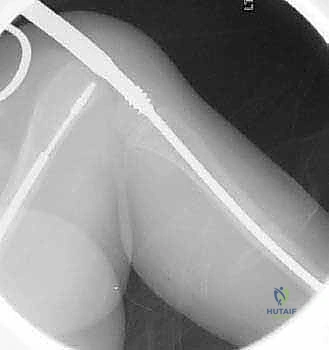

يتم إجراء العملية تحت التخدير العام. يتم وضع الطفل على طاولة العمليات الشفافة للأشعة، ويتم استخدام جهاز الأشعة السينية المستمر (C-arm) لضمان الدقة المطلقة خلال كل ثانية من العملية.

الخطوة الثالثة: بضع العظم المتعدد عبر الجلد (Multiple Percutaneous Osteotomies)

بدلاً من فتح الساق بالكامل، يقوم الدكتور هطيف بعمل ثقوب صغيرة جداً (مليمترات) في الجلد. باستخدام أدوات دقيقة جداً (مثل الإزميل الدقيق أو المثقاب المتخصص)، يتم قطع العظم في أماكن التقوس من الداخل دون إتلاف الأنسجة الرخوة أو العضلات المحيطة. هذا يحافظ على التروية الدموية للعظم (Periosteum)، مما يسرع من التئام العظم بشكل مذهل.

الخطوة الرابعة: إدخال المسمار التلسكوبي

بعد تقويم العظم وجعله مستقيماً كحبات المسبحة على خيط، يتم إدخال السلك الدليلي (Guide Wire). ثم يتم إدخال الجزء الخارجي (الأنثوي) من المسمار التلسكوبي وتثبيته في الجزء العلوي من العظم (Epiphysis).

بعد ذلك، يتم إدخال الجزء الداخلي (الذكري) من المسمار عبر الجزء السفلي من العظم وتثبيته في المشاشة السفلية. هذا التصميم العبقري يضمن حماية العظم بالكامل من الداخل.